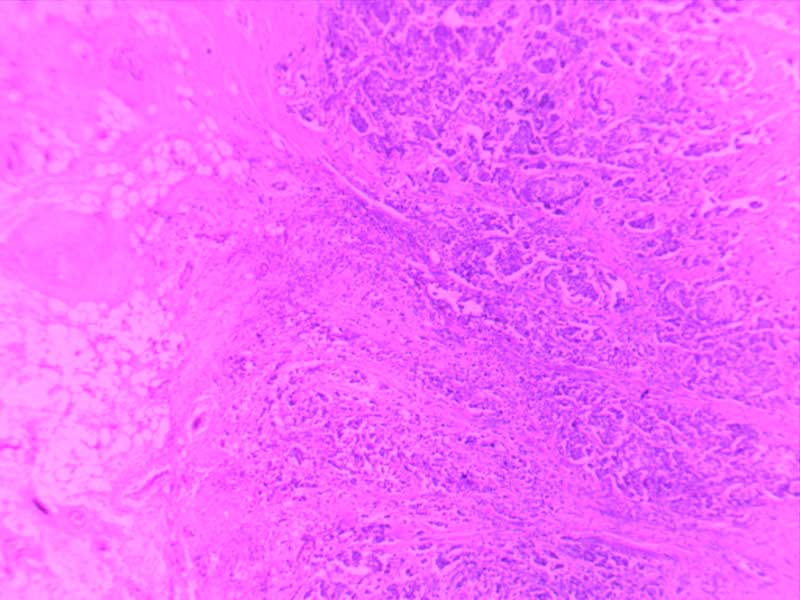

绒毛膜癌-10倍

肉芽组织-10倍

乳头状瘤(膀胱)4倍

乳腺癌-4倍

乳腺癌-10倍

神经鞘瘤4倍

神经鞘瘤-10倍-(2)

神经鞘瘤-10倍

大叶性肺炎(红肝期)10倍

大叶性肺炎(红肝期)-10倍

大叶性肺炎(灰肝期)-4倍

大叶性肺炎(灰肝期)-10倍